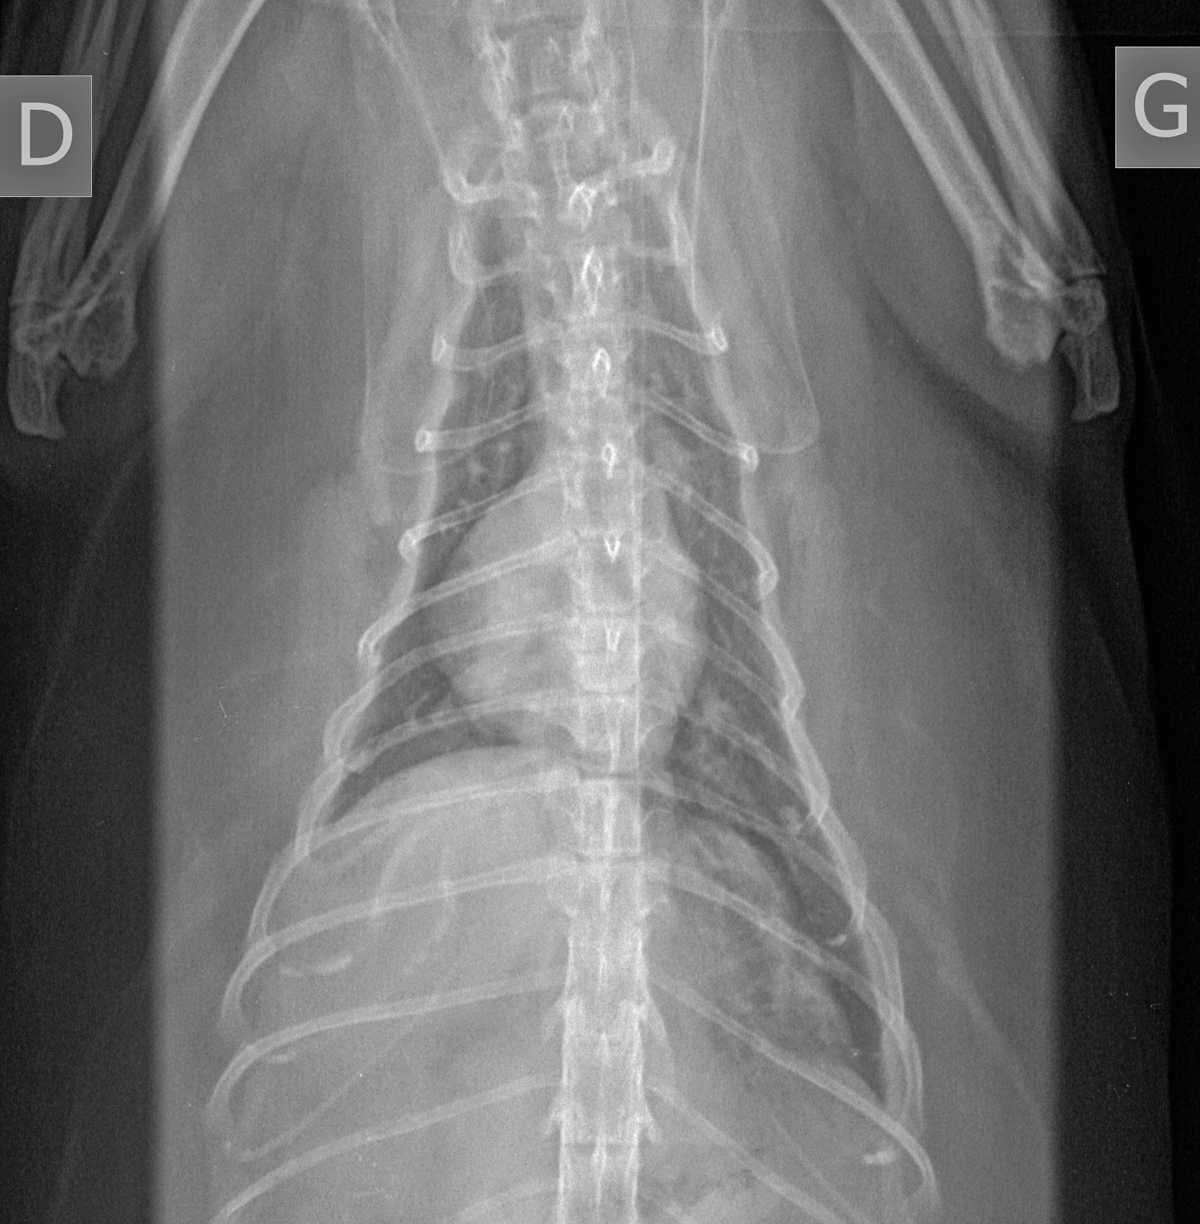

Signalement: chatte domestique calico stérilisée de 11 ans.

Histoire clinique: Anorexique et abattue depuis deux semaines, avec toux occasionnelle. Depuis 24-48 heures, ne file vraiment pas.